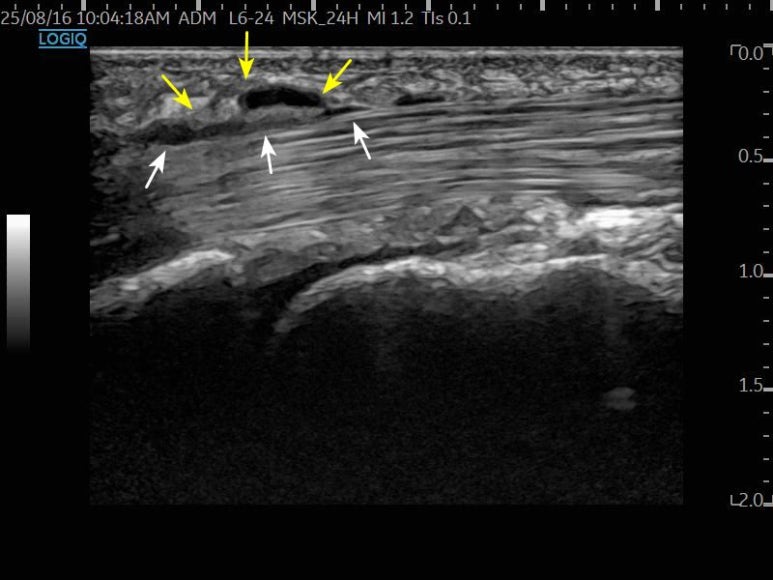

먼저, 손가락 힘줄의 움직임을 실시간으로

살펴보겠습니다.

손가락을 구부릴 때마다

부어있는 활차로 인해 힘줄이 두꺼워지는게

보이시나요?

바로 저 위치에서 힘줄이 끼어

옴짝달싹 못하게 되는 것이죠.

이렇게 문제가 생긴 힘줄과 활차를

정확하게 찾아낸 뒤,

염증으로 유착된 부분은 으로 박리하고요.